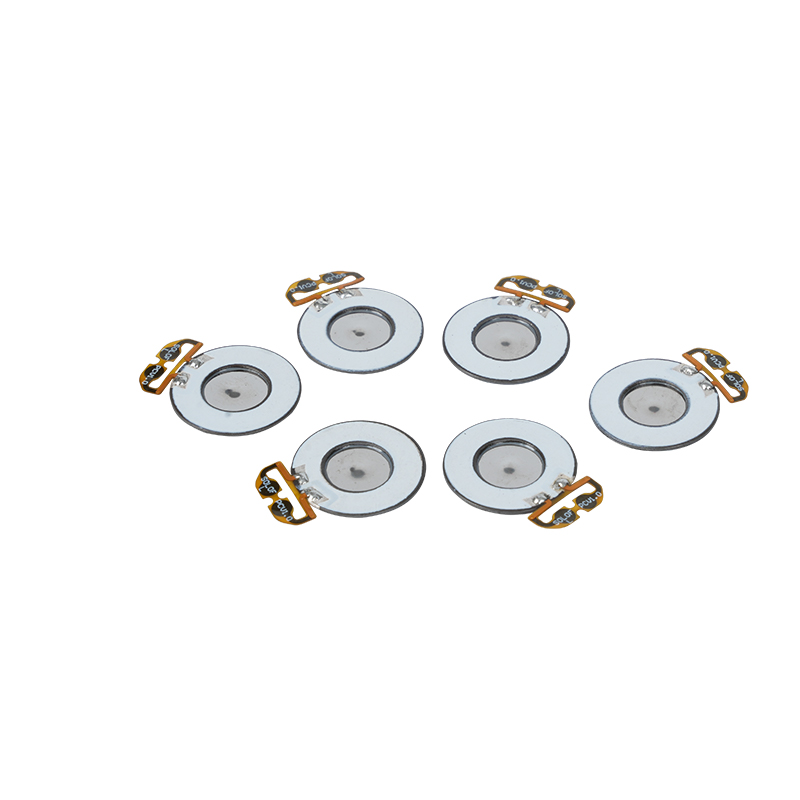

Medical Mesh Nebulizer Tablets zijn precisiecomponenten die in medische apparaten worden gebruikt om medicijnen of oplossingen om te zetten in kleine aërosoldeeltjes voor de behandeling van verschillende ademhalingsaandoeningen zoals astma en chronische obstructieve longziekte (COPD), enz. door inhalatie. Het ontwerp en de materiaalkeuze van het vernevelblad zijn van cruciaal belang om een effectieve medicijntoediening en comfort voor de patiënt te garanderen. De roestvrijstalen membraanplaat wordt met duizenden kleine gaatjes van 2-3 μm in de staalplaat geponst door middel van laserboortechnologie in een nauwkeurig laserproces, en vervolgens wordt het stevig verbonden met de piëzo-elektrische keramische ronde plaat, die de resonantiefrequentie van de piëzo-elektrische plaat omzet in hoogfrequente trillingsenergie via het uitgangssignaal van de PCB-stuurkaart, en de vloeibare medicatie snel afbreekt. in fijne aërosoldeeltjes. Deze druppeltjes worden ook wel de gemiddelde deeltjesgrootte genoemd. Wanneer het gemiddelde D50-percentage van de deeltjesgrootte >60% of meer bereikt, zullen de deeltjes klein genoeg zijn om met ademhaling diep in de longen tot aan het oppervlak van de longblaasjes te kunnen reiken, waardoor de absorptie-efficiëntie van de medicatie en het therapeutische effect worden verbeterd. Medical Mesh micro mesh vernevelaarblad heeft voornamelijk verschillende vormen, roestvrijstalen micro mesh vernevelaarblad, nikkel palladium medische vernevelaarblad, PI-polymeer medische vernevelaarblad, enzovoort. Al het bovenstaande gebeurt via de piëzo-elektrische keramische trillingsenergieconversie om het vernevelingseffect te bereiken.

Polyimide (Polyimide), ook wel PI genoemd, is de beste uitgebreide prestatie van organische polymeermaterialen, het heeft een uitstekende chemische stabiliteit en is bestand tegen de corrosie van een verscheidenheid aan medicijnen, om langdurig gebruik van de prestaties van verstoven tabletten te garanderen. Bovendien is de thermische stabiliteit van polymeer PI-film ook uitstekend, met langdurig gebruik van temperatuurbereik -200 ~ 300 ° C, hoge isolatie, milieubescherming en niet-toxiciteit, als een speciaal technisch materiaal, dat veel wordt gebruikt in de ruimtevaart, micro-elektronica, nano-vloeistofkristalscheidingsmembranen en andere gebieden, werd in de 21e eeuw opgenomen door de landen van een van de meest veelbelovende technische materialen, en het is niet gemakkelijk om te worden vervormd tijdens het desinfectieproces op hoge temperatuur, om ervoor te zorgen dat het product opnieuw wordt gebruikt! Voor seks en veiligheid gebruiken we lasertechnologie voor laserperforatie, PI-film geïmplanteerd tussen het roestvrij staal en de piëzo-elektrische plaat, het gebruik van piëzo-elektrische keramische ultrasone technologie zodat de vernevelde druppels door de PI-film worden verspreid in de verneveling van 3 ~ 4 μm-deeltjes voor medische verneveling, de veiligheid van de meerderheid van de gebruikers is dol op, gemaakt van de vernevelaar met de PI's belangrijkste voordeel van niet-verstopping, de binnenwand van het gat is glad en afgerond, geen residu van de vloeistof, de verneveling van fijn en stabiel. De verneveling is delicaat en stabiel. PI-filmverneveltabletten kunnen medicijnresten effectief voorkomen en het risico op kruisbesmetting verminderen. In de praktijk worden de eigenschappen van het lage energieverbruik van polymeer PI-membraanverneveltabletten ook weerspiegeld. Kortom, polymeer PI-membraanverneveltabletten zijn met hun uitstekende prestaties en ontwerpvoordelen een onmisbaar onderdeel geworden op het gebied van medische vernevelingstherapie.